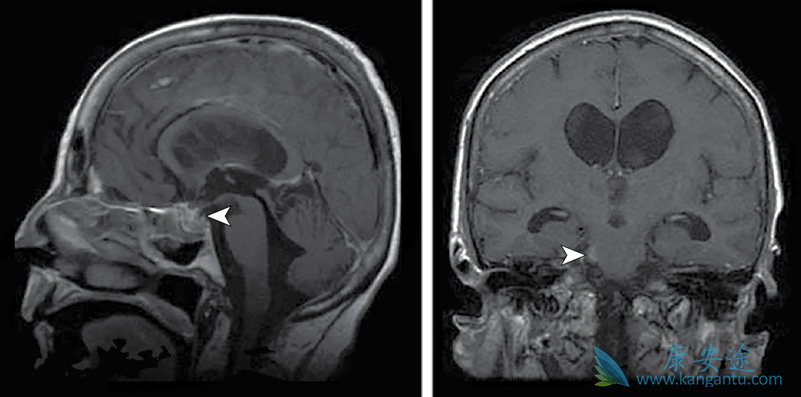

肺癌发展到了晚期,经常会出现转移,根据转移的不同部位,会产生不同的症状,而超过一半的肺癌可能出现脑转移,那么,出现肺癌脑转移能活多久?肺癌脑转移患者预后差,自然平均生存时间仅 1~2 个月。专家表示,肺癌脑转移是晚期肺癌较常出现的现象。临床数据表明,一半以上的肺癌会出现脑转移。有数据统计显示,脑转移的患者,存活期不超过一年。肺癌脑转移的治疗已经成为临床关注的热点之一。

各组织学类型肺癌脑转移的发生率存在差异,一项美国长期随访结果显示,在非转移性非小细胞肺癌(non-small cell lung cancer,NSCLC)中,肺腺癌、鳞癌及大细胞癌发生脑转移的风险分别为11%、6%及12%。小细胞肺癌(small cell lung cancer,SCLC)首次就诊时脑转移发生率为10%,诊疗过程中为40%-50%,存活2年以上的患者脑转移达60%-80%,是影响SCLC患者生存及生活质量的重要因素之一。